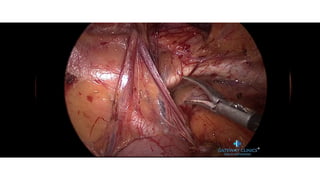

LEFT POSTERIOR LATERAL

DEFECT

CONTENTS ADHERANT TO THE SAC

EXPOSURE OF THE HIATUS

DEFECT CLOSURE

MESH PLACEMENT

Left Posterolateral Defect In Adult

DEFECT CLOSURE AND MESH PLACEMENT